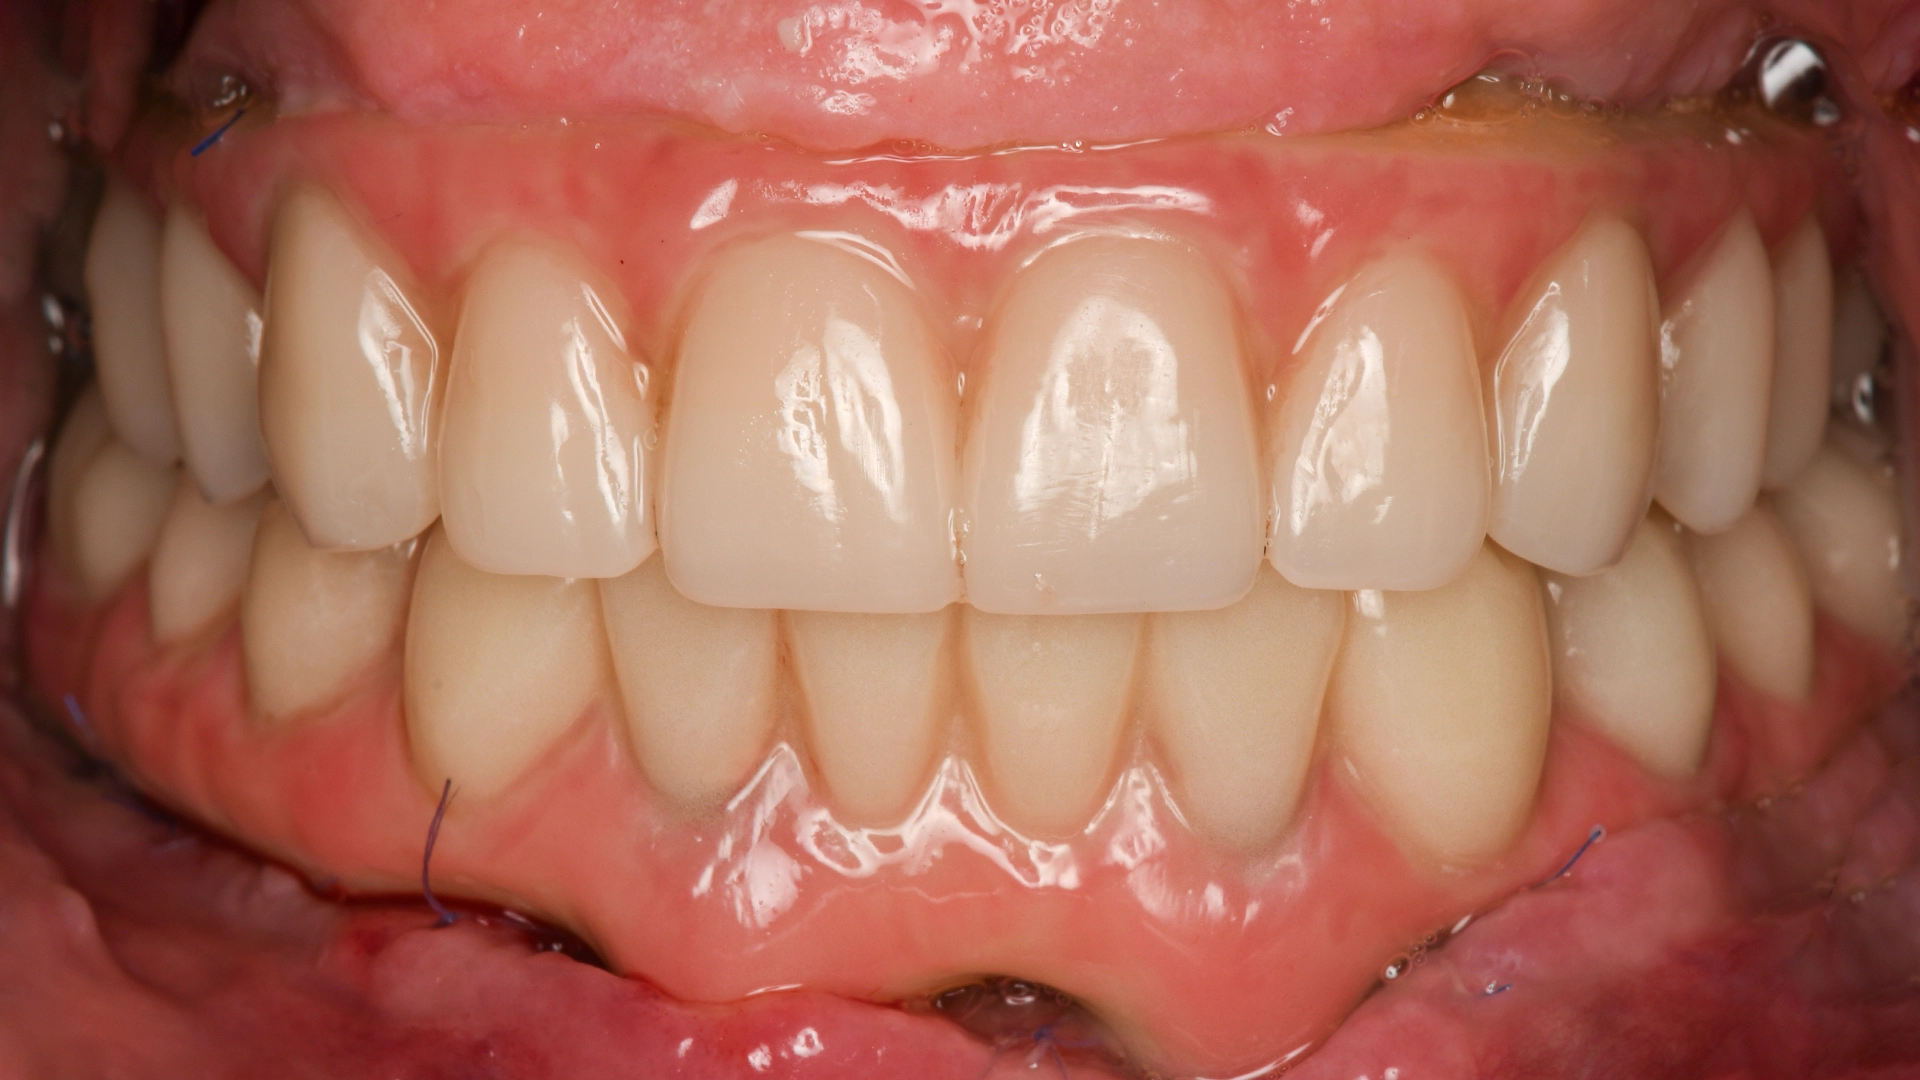

After dental implant – natural smile result at VIDENT Antwerp

Before After

after 5 years follow up

After dental implant – smile transformation at VIDENT Antwerp